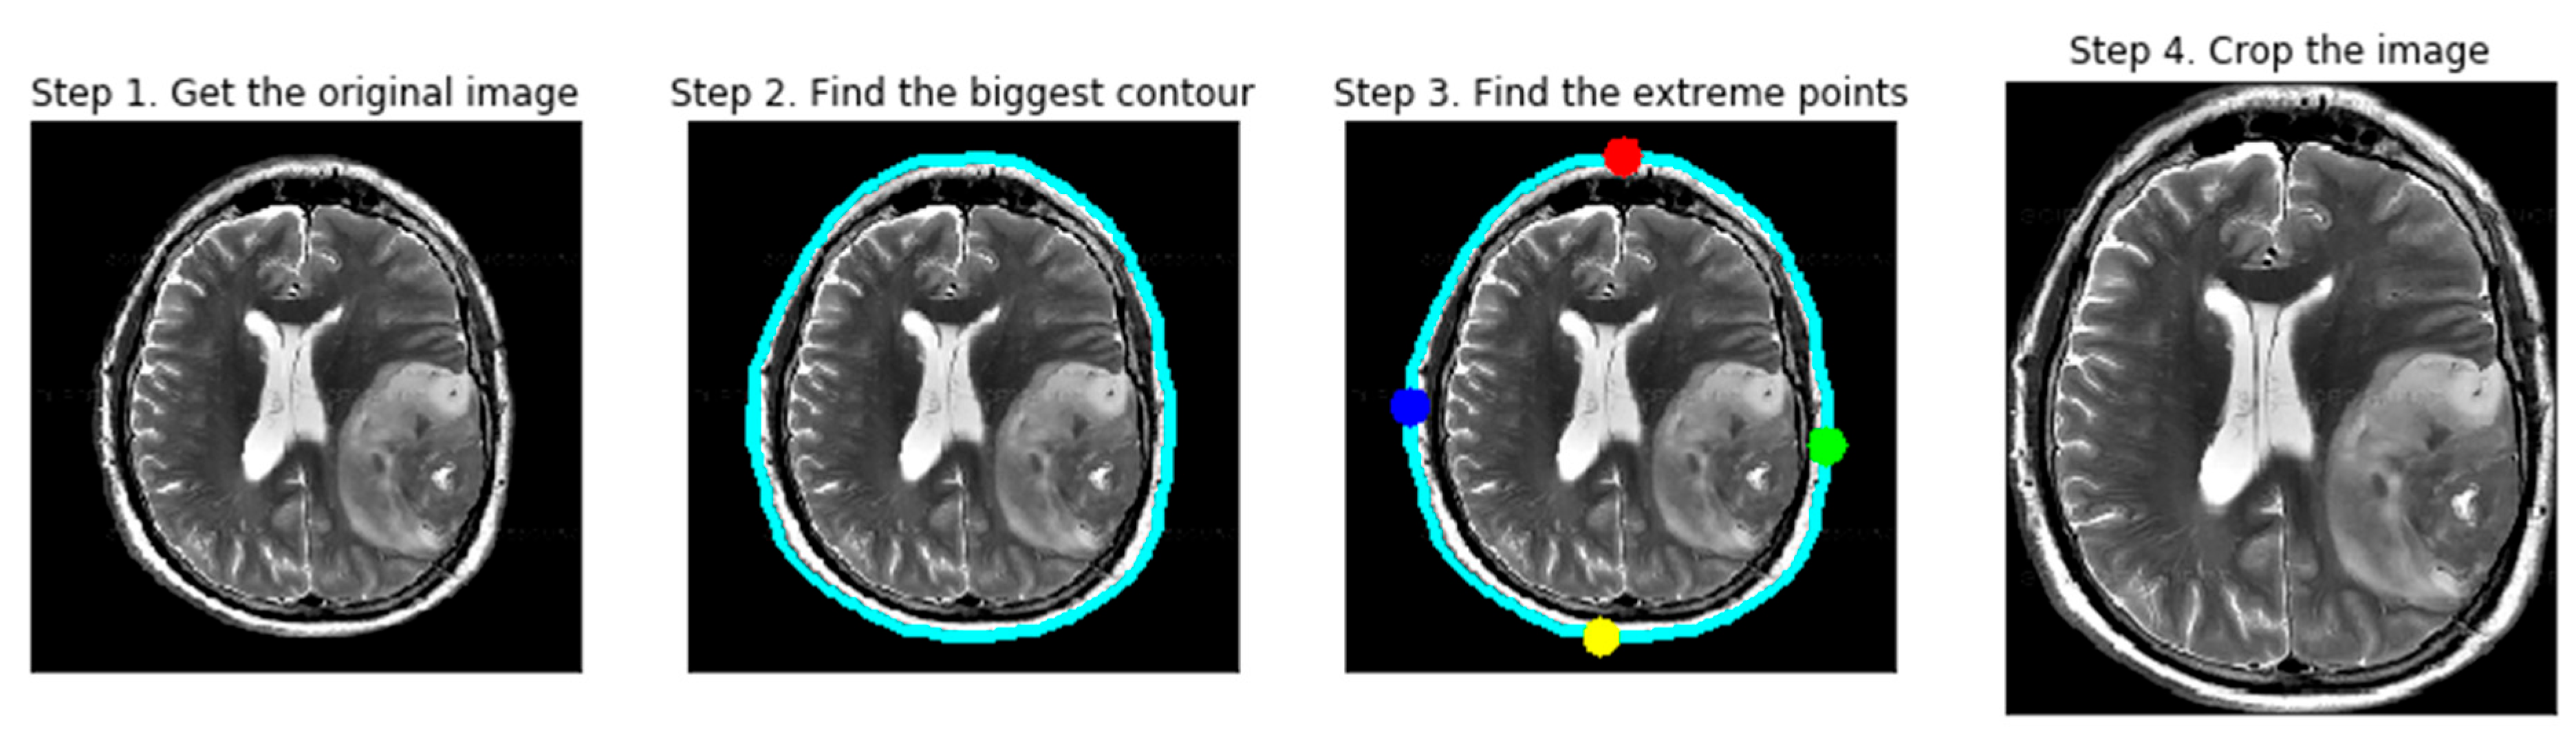

Data preparation is a critical component of medical image analysis, as it directly influences model accuracy and robustness. In this study, MRI images underwent a series of preprocessing steps—including contour-based cropping, dilation, and erosion—to reduce noise and artifacts and to enhance classifier performance. Cropping was conducted using a contour detection system that identifies extreme points and curves to isolate the region of interest. Figure 2 presents representative examples of cropped brain tumor images obtained using parameter-based calculations.

Although the present framework is limited to MRI-based analysis, it has the potential to incorporate additional biomechanical features and multimodal data in future research, such as integrating ultrasound imaging to improve diagnostic precision. As illustrated in Figure 3, raw MRI images from the BR35H dataset were imported and subjected to preprocessing. Initially, all RGB images were converted to grayscale, followed by binary conversion through thresholding. Subsequently, dilation and erosion operations were applied to minimize minor interferences and enhance structural boundaries. Contours were then detected on the thresholded images, and the largest contour was selected to determine the extrema points, which were used to crop the final region of interest.

Figure 3. Sample image preprocessing.

Ai 06 00305 g003